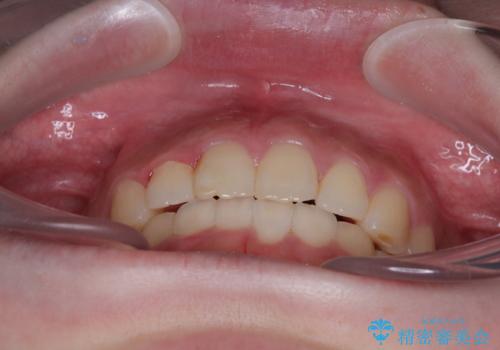

前歯のデコボコをインビザラインできれいに整える

- 前歯のデコボコと上下の隙間を気にして来院された患者様です。

前歯の捻れを改善するとともに、口元が少しでも引っ込むように治療計画を立て、仕上げることができました。